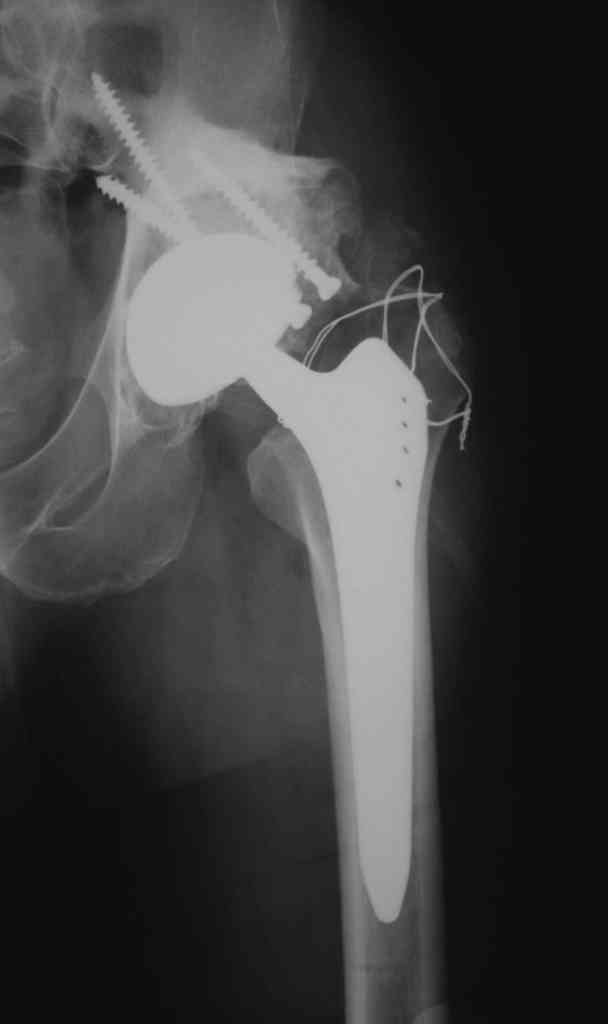

Еще одно наблюдение, неправильно сросшийся перелом заднего отдела ВВ с ввихом головки бедра 16-и летней давности.